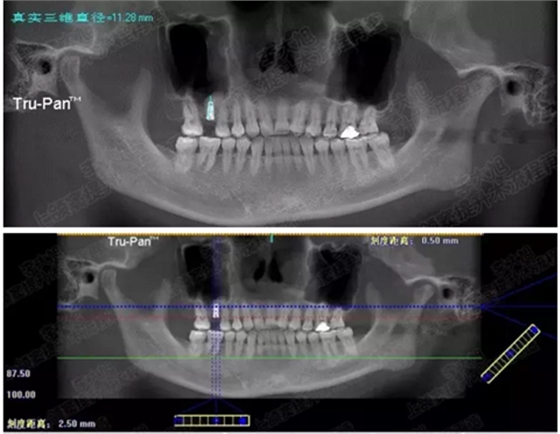

病例三

剩余骨量3mm

005.png

006.png